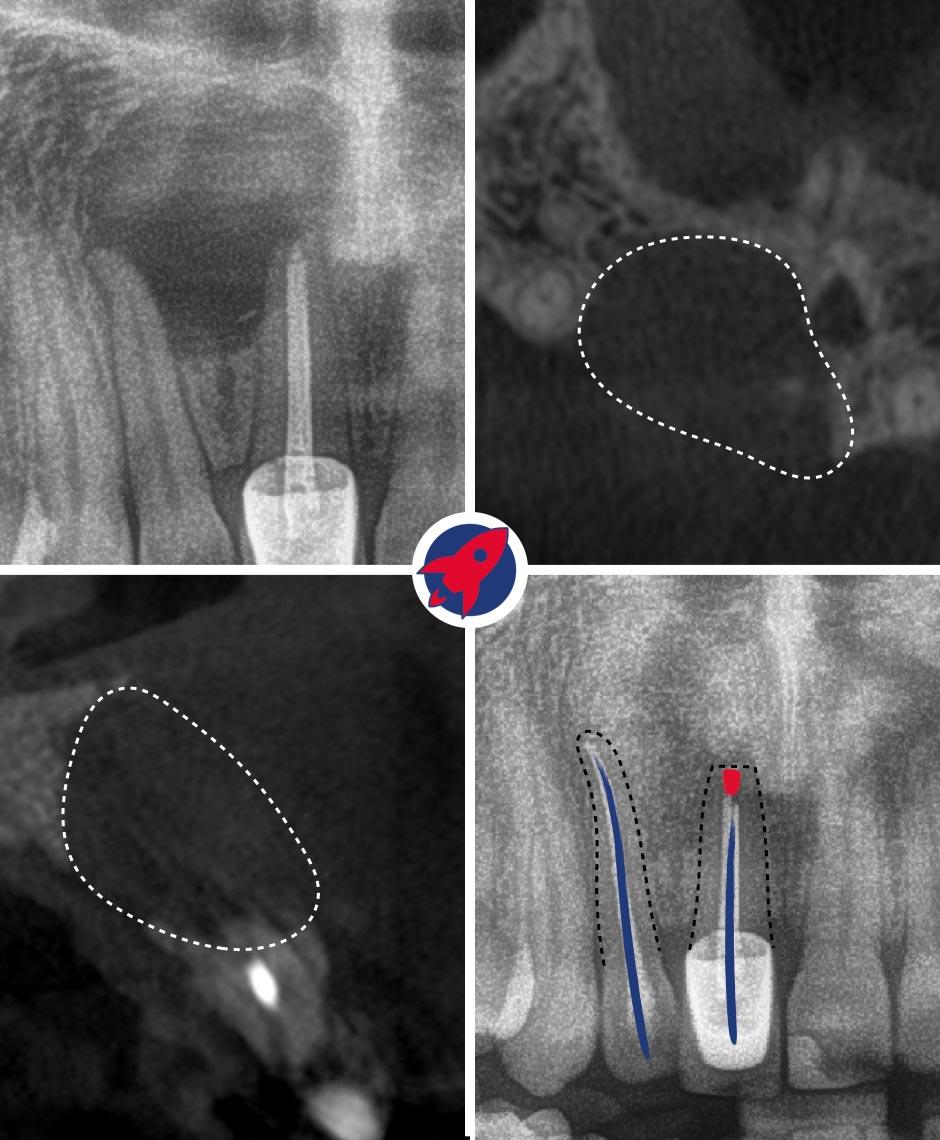

Treatment Under the Dental Microscope

The core of our endodontics. The up to 25x magnification enables the visualization of the finest canals, which are impossible to find with the naked eye.

Cleaning Under the Microscope

The tooth is isolated. Using the X-ray and the magnification of the microscope, the canals are opened, flushed, and cleaned and disinfected with machine-driven instruments down to the tip.